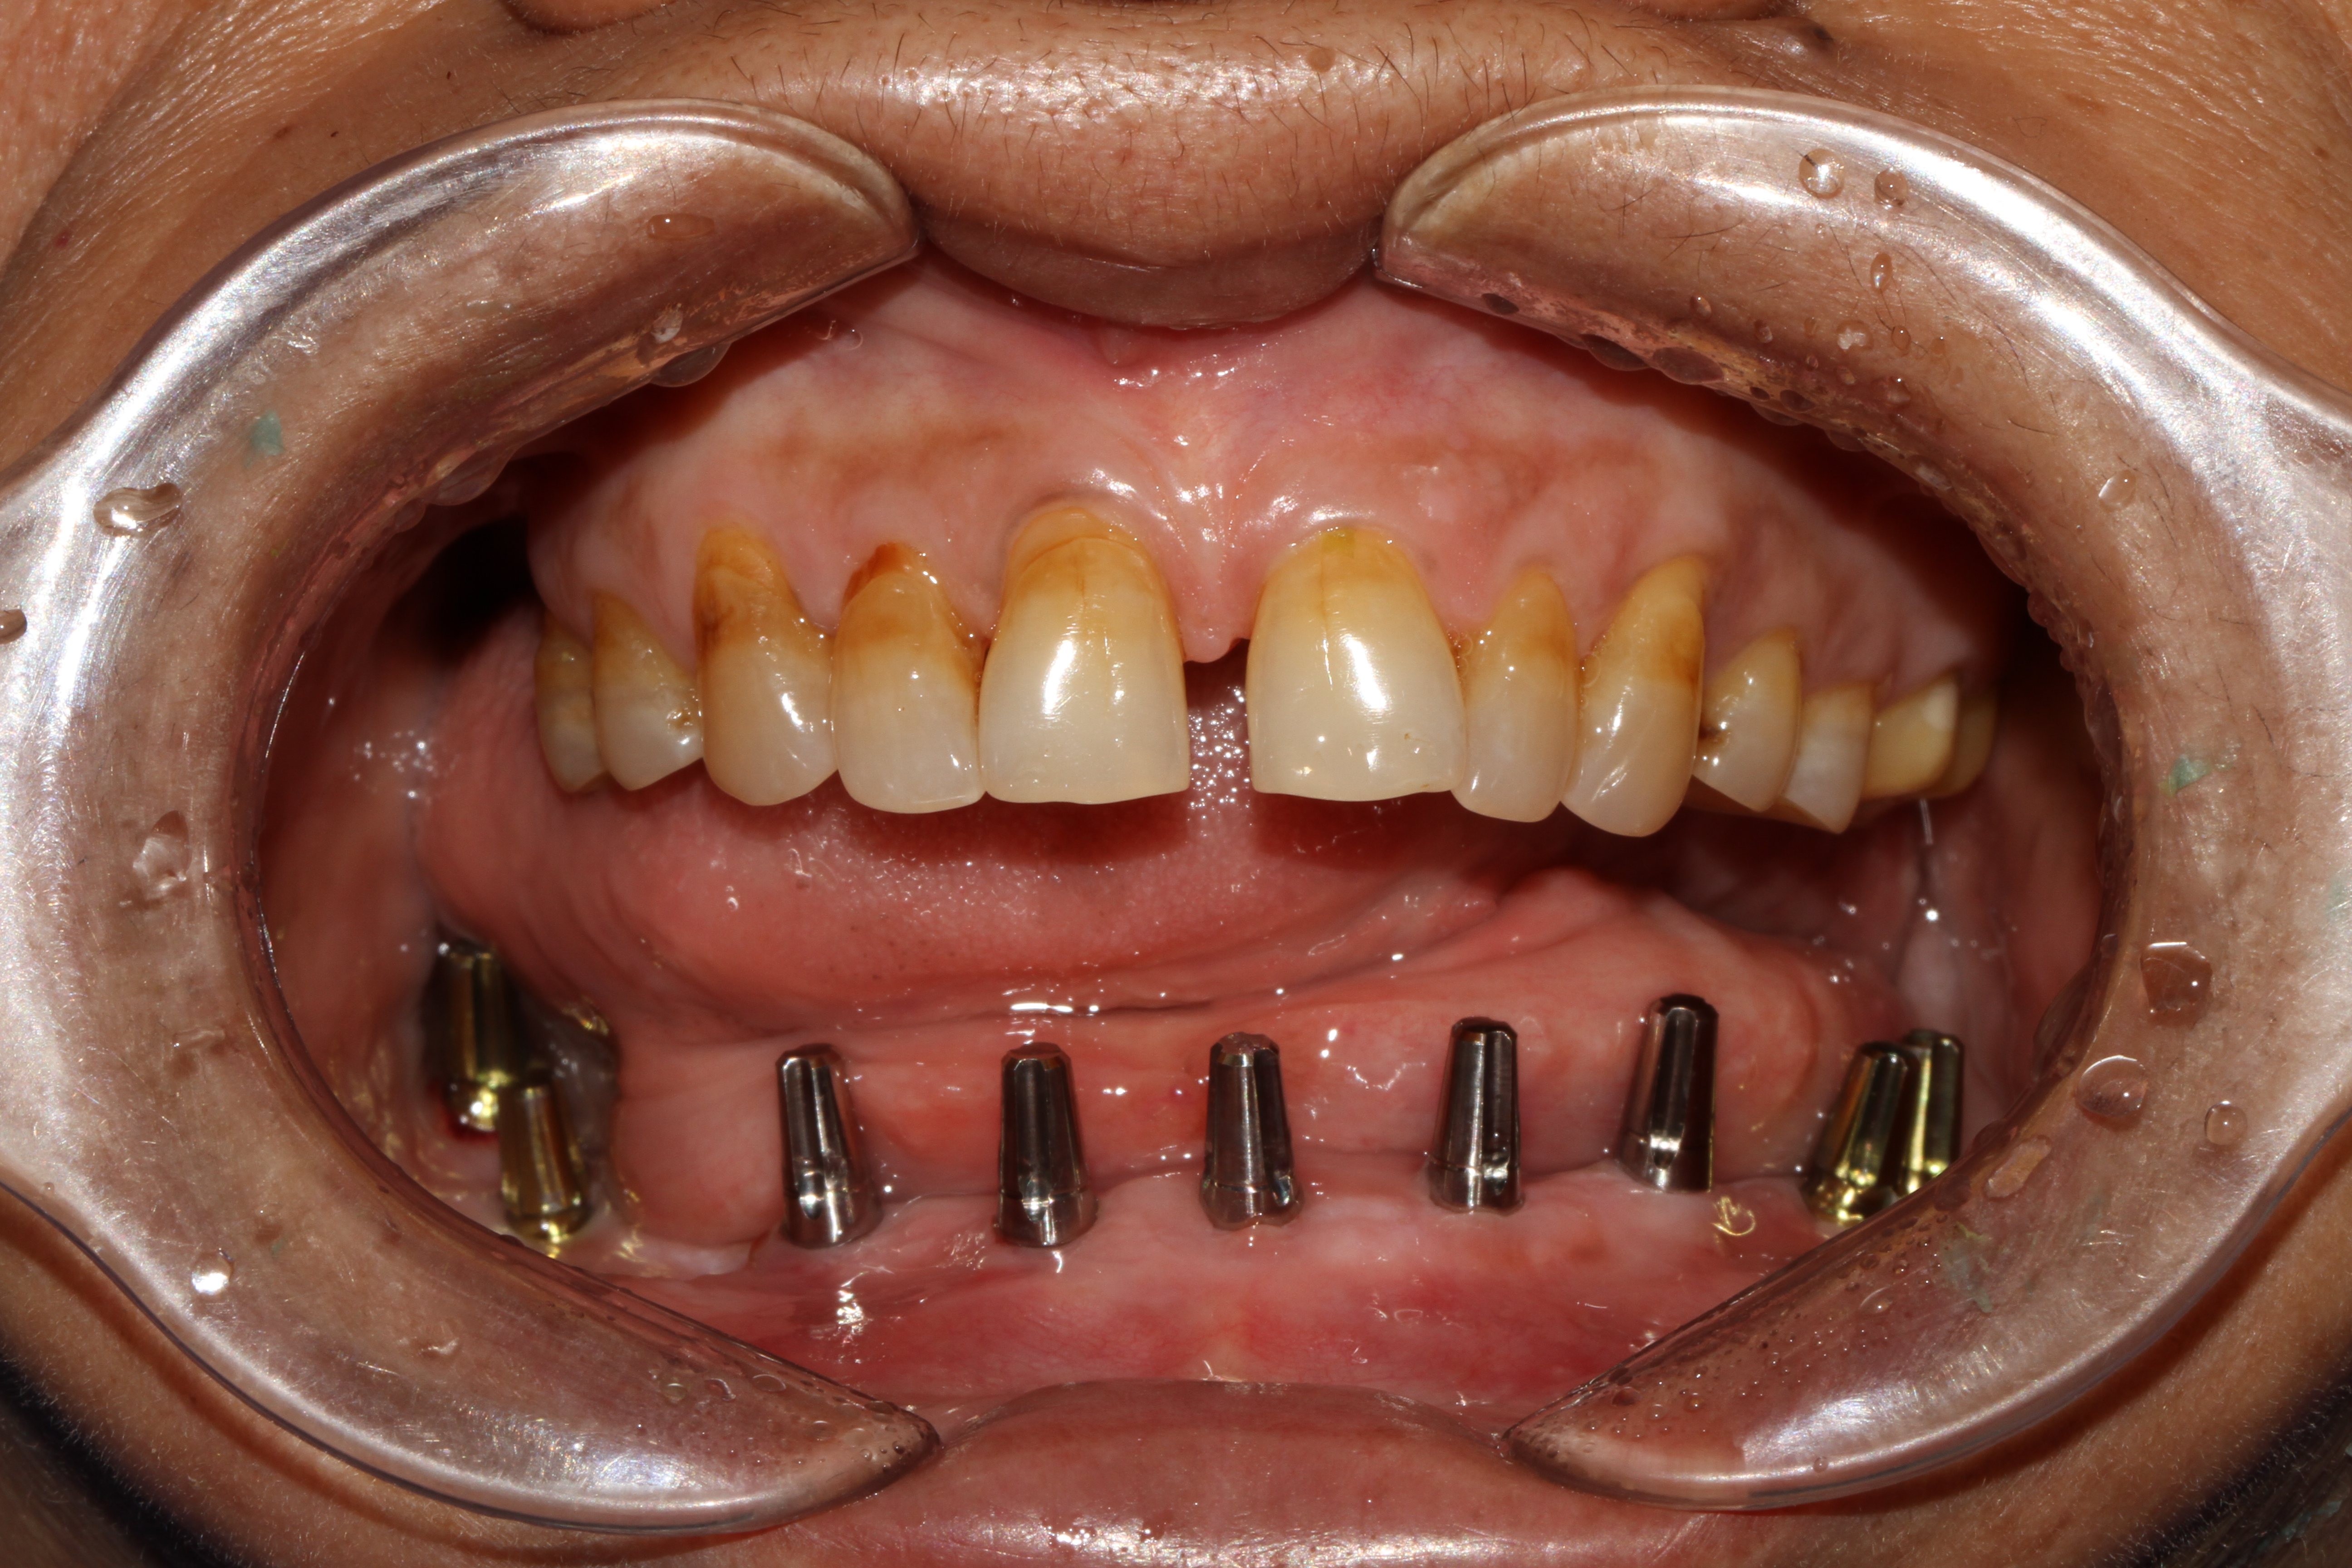

LOWER JAW (FULL ARCH)

FIXED OPTIONS FOR A FULL ARCH REPLACEMENT IN LOWER JAW

When it comes to replacing the entire arch of a lower jaw with 14 teeth, options like replacement with a zirconia crown, which is free of metal or porcelain fused to metal (ceramic) crown can be used. These crowns are fabricated in our hi-tech lab in 3 days which is fixed with the new generation of immediate loadable single piece implant. At Jani's Implant Cantre and Smile Studio, basal implants with a combination of crestal implants are used. Using this art of implant placement all 14 teeth which include the second molars are replaced. The introduction of second molars by this step will help the patient chew in a more efficient way similar to that of natural teeth. depending upon the patient's medical status, oral health and the quality of the bone, 6-8 implants are placed on which 14 teeth (full arch) is fixed. This is a full mouth immediate loadable implant therapy for the lower jaw. This is done in the form of permanent teeth in 3 days protocol where no bone augmentation and bone grafting is needed.